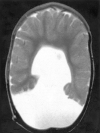

Background and purpose: Analysis of specific features in the brain of patients with holoprosencephaly (HPE) may clarify normal and abnormal brain development and help predict outcomes for specific children. We assessed sulcal and gyral patterns of cerebral cortex in patients with HPE and developed a method of grading brain development.

Methods: Neuroimaging studies (75 MR imaging, 21 CT) of 96 patients with HPE were retrospectively reviewed, with specific attention paid to the cerebral cortex. Thickness of cortex, width of gyri, and depth of sulci were assessed subjectively and by measurement. The angle between lines drawn tangential to the sylvian fissures ("sylvian angle") was measured in each patient with HPE and in 20 control patients.

Results: Thickness of cortex was normal in all 96 patients. Gyral shape and width and sulcal depth were normal in 80 patients. Twelve patients, all with very severe HPE and microcephaly, had reduced sulcal depth, diffusely in eight and limited to the anteromedial cortex in four with lobar HPE. Four patients had subcortical heterotopia, located anterior to the interhemispheric fissure, associated with shallow sulci in the overlying cortex. Sylvian fissures were displaced further anteriorly and medially as HPE became more severe, until, in the most severe cases, no sylvian fissures could be identified. Sylvian angle measurements corresponded closely with severity of HPE, being largest in the most severe and smallest in the least severe cases. All patients with HPE had sylvian angles significantly larger than the mean of 15 degrees measured in the control patients.

Conclusion: The only true malformations of cortical development were subcortical heterotopia. However, diffuse and focal abnormal sulci were observed. We propose our sylvian angle measurement of extent of frontal lobe development as an objective means of quantifying the severity of HPE.